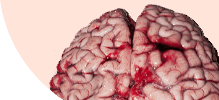

ГЕЛЬМИНТЫ ПОРАЖАЮТ ИЗНУТРИ, РАЗМНОЖАЮТСЯ И ВЫЗЫВАЮТ СМЕРТЕЛЬНЫЕ ЗАБОЛЕВАНИЯ!

Самки паразитов откладывают до 240 000 яиц в кишечнике человека ежедневно.

Размеры гельминтов (глистов) колеблются от нескольких сантиметров до 7-10 метров.